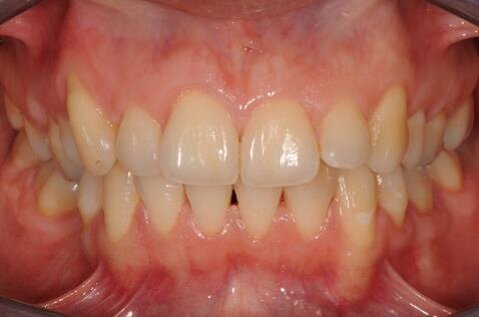

In questo modo è stato possibile ottimizzare i tempi, impiegando il periodo dell’ossointegrazione per completare la terapia ortodontica. Ulteriore ottimizzazione dei tempi è stata possibile rimuovendo, un mese prima del termine della terapia ortodontica, gli “engagers” ed utilizzando gli allineatori come “carriers” per un gel sbiancante (Opalescence PF 10% - Ultradent Products Inc – South Jordan, Utah, USA) applicato dalla paziente nelle ore notturne (circa 8 ore al giorno) per 12 notti consecutive, al termine delle quali il risultato è apparso soddisfacente. Al termine della terapia ortodontica sono state rilevate le impronte in polivinilsilossano per la realizzazione della corona in posizione 4.6. Dato lo spazio mesiodistale ridotto, si è proceduto con la realizzazione di una corona di dimensioni corrispondenti ad un premolare (Figg. 6a-7). Al termine delle procedure protesiche sono state realizzate due mascherine di contenzione ed è stato prescritto il loro impiego solo per le ore notturne.

Figg. 6a-6d - Foto intraorali post-trattamento: visioni frontale (a), laterali (b), occlusali (c, d).